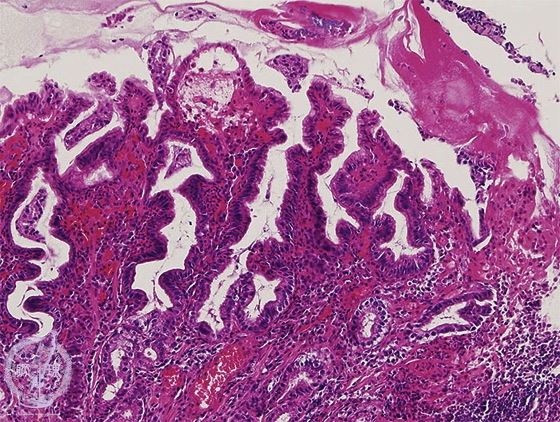

Microscopic view (H&E stain, intermediate power): Acute gastric mucosal lesions. The glandular epithelium is darkly staining and conspicuously tortuous; However, the architectural integrity is preserved, consistent with regenerative change.